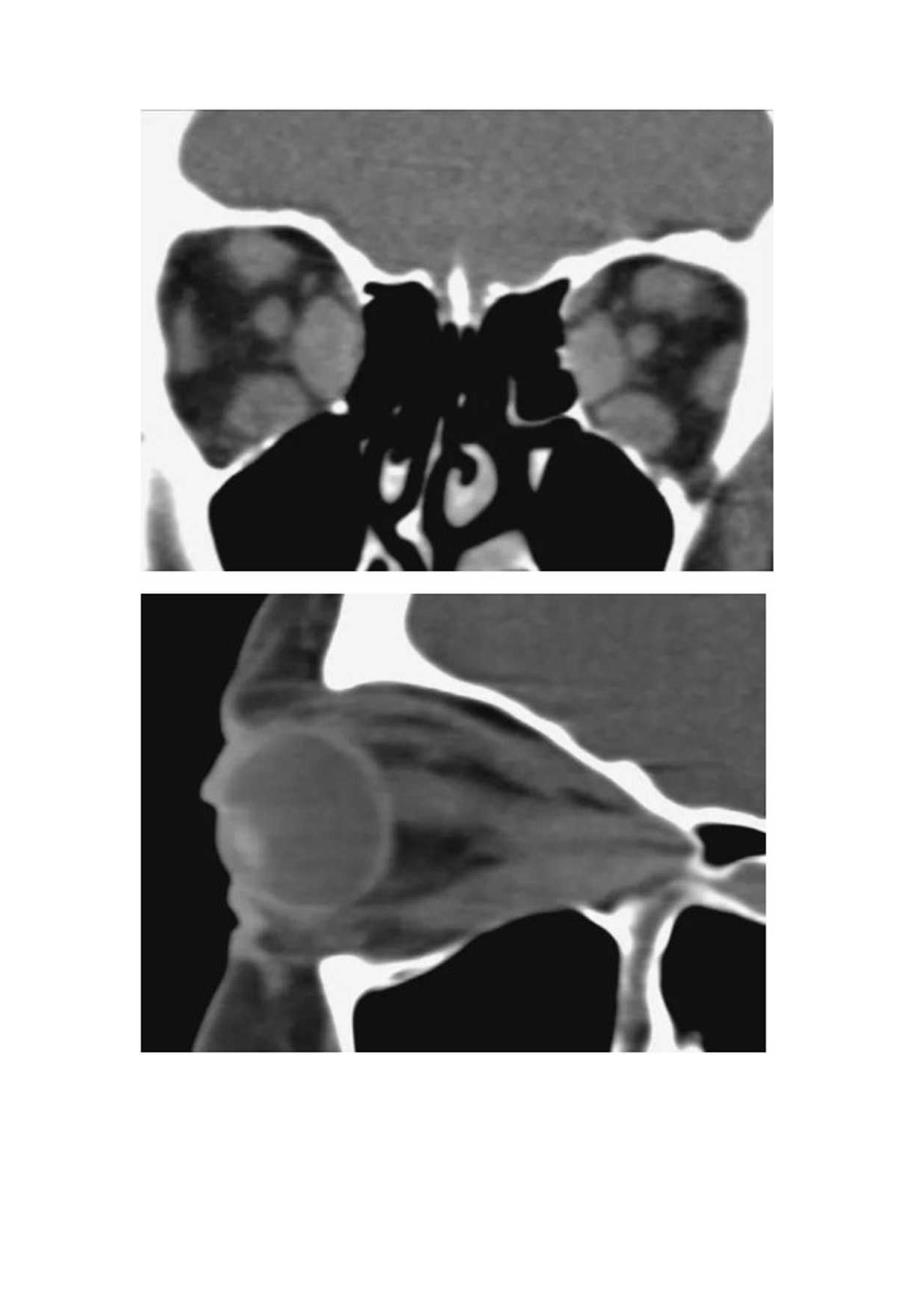

1、临床眼眶炎性假瘤病理、影像学表现及鉴别诊断可乐瓶征指轴位扫描时甲状腺眼病(thyroideyedisease)中眼眶肌肉的外观,肌腹随着肌腱插入的增加而扩大、增粗,肌腱附着处正常,表现为传统可口可乐瓶的样子。尤其是内直肌的增粗,且眶内侧壁骨质菲薄,长期眶压升高,致筛骨纸板向筛窦弧形凹陷,双侧对称。肌肉的增粗遵循缓慢模式IWS1.OW”。肌肉增粗的性质十分重要,是将其与眼眶炎性假痛区分开来的主要表现之一,与甲状腺眼病不同,炎性假痛的肌瞰也受累并增粗。甲亢突眼是成年人最常见的眼眶病之一,属于自身免疫性疾病。大多数患者可有甲状腺功能异常的临床或实验室检杳表现,但即使在甲状腺功能正常的情况下,也可能发

2、生眼眶疾病。甲状腺相关眼病是引起单眼或双眼突出的常见原因。在急性期,主要的原发改变是炎症,由于眼外肌肥大和眶脂肪容积增加而导致的体积效应,以及肌肉改变产生的运动受限。其次为眼应依从性的改变和由于眼眶缺乏淋巴回流而导致不同程度的瘀血。影像表现:1、冠状位可显示各条眼外肌增粗,甚至少数患者可累及上、下斜肌。2、轴位可较好的显示内、外直肌增粗,睚内侧壁骨质菲薄,长期眶压升高,致筛骨纸板向筛窦弧形凹陷,双侧对称,呈“可乐瓶”征。3、眼球突出严重者,视神经受到牵拉失去生理弯曲,呈直线状。re出力外t联线B为仃角黑到灰线的n即IIlII7夹电,EF为左窜”夹电中m人正常眼球突出度双限在I”ISl鉴别诊断:

3、肌炎型炎性假瘤疼痛无痛性突眼活动性疼痛病程发病缓慢多急性甲功异常正常激素治疗无效有效肌腹和肌腱同时增粗,且形态不规则眠后脂肪间隙受累,可伴视神经增粗、眼环增厚眼外肌改变肌腹增粗为主,肌腱附着处正常眶内结构受累多无随后脂肪间隙受累及视神经培粗眼眶炎性假痛(Orbitalpseudotumor)或称特发性眶部炎症,0前多数学者认为炎性假瘤是一种免疫反应性疾病。炎症表现为急性、亚急性或慢性,可单侧或双侧交替发生。病变部位可局部发生;但常多部位发生,包括肌炎、泪腺炎、巩膜周围炎、视神经鞘炎,多伴有脂肪炎性浸润。肌炎型表现为:一条或数条眼外肌增粗,以上直肌和内直肌多见,典型者为肌腱和肌腹同时增粗,边缘多模糊,不整齐。